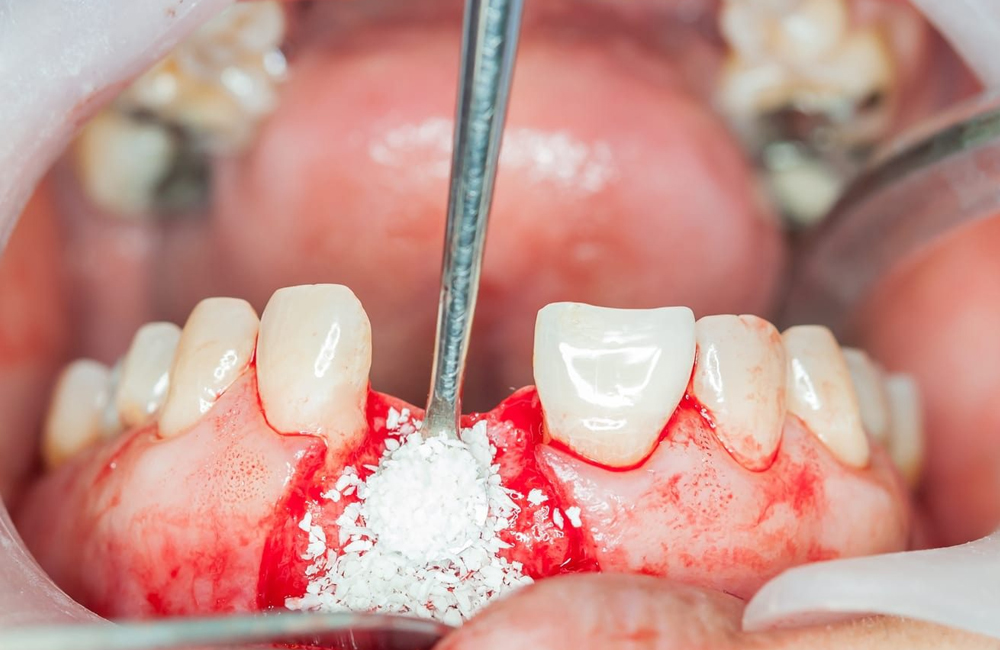

در تکنیک GTR، پودر استخوان معمولاً بهعنوان فیلر (Filler) یا اسکافولد (Scaffold) در زیر غشا قرار میگیرد. نقشهای اصلی آن عبارتاند از:

حفظ فضا (Space Maintenance):

یکی از چالشهای GTR جلوگیری از فروپاشی غشا و تماس آن با بافت نرم است. پودر استخوان با پر کردن حفره، ساختار سهبعدی مورد نیاز برای حفظ فضا را فراهم میکند.القا و هدایت رشد استخوانی: